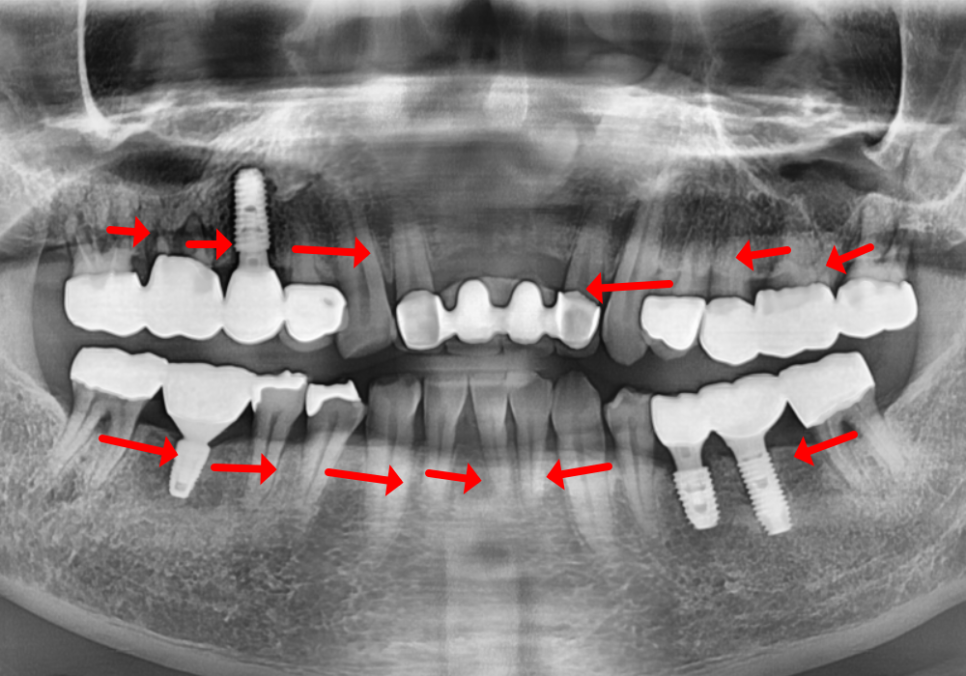

임플란트 주위 부분이 빨간 삼각형,

자연치아 주위 부분이 노란 삼각형일 때

빨간 삼각형이 노란 삼각형보다

훨씬 커보이죠?

이렇듯 자연치보다 임플란트 주위의

공간이 크다보니 음식물이 더 잘 끼게 됩니다.